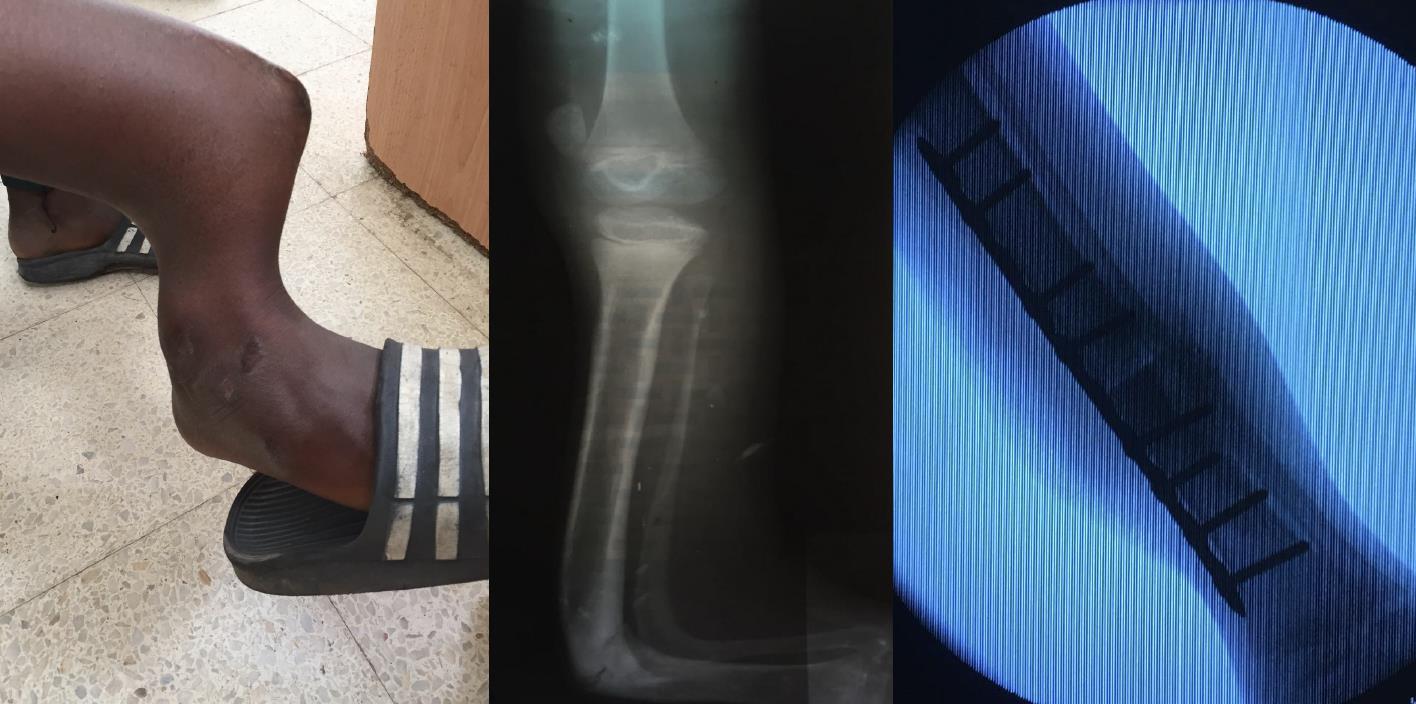

In the Gambia many patients with injuries use traditional medicine and healers.

Fractures are often bound with sticks and can go on to mal-unite resulting in significant permanent deformity.

The resulting deformities would pose a significant orthopaedic challenge to reconstruct the limb in the Western World, let alone in the Gambia.